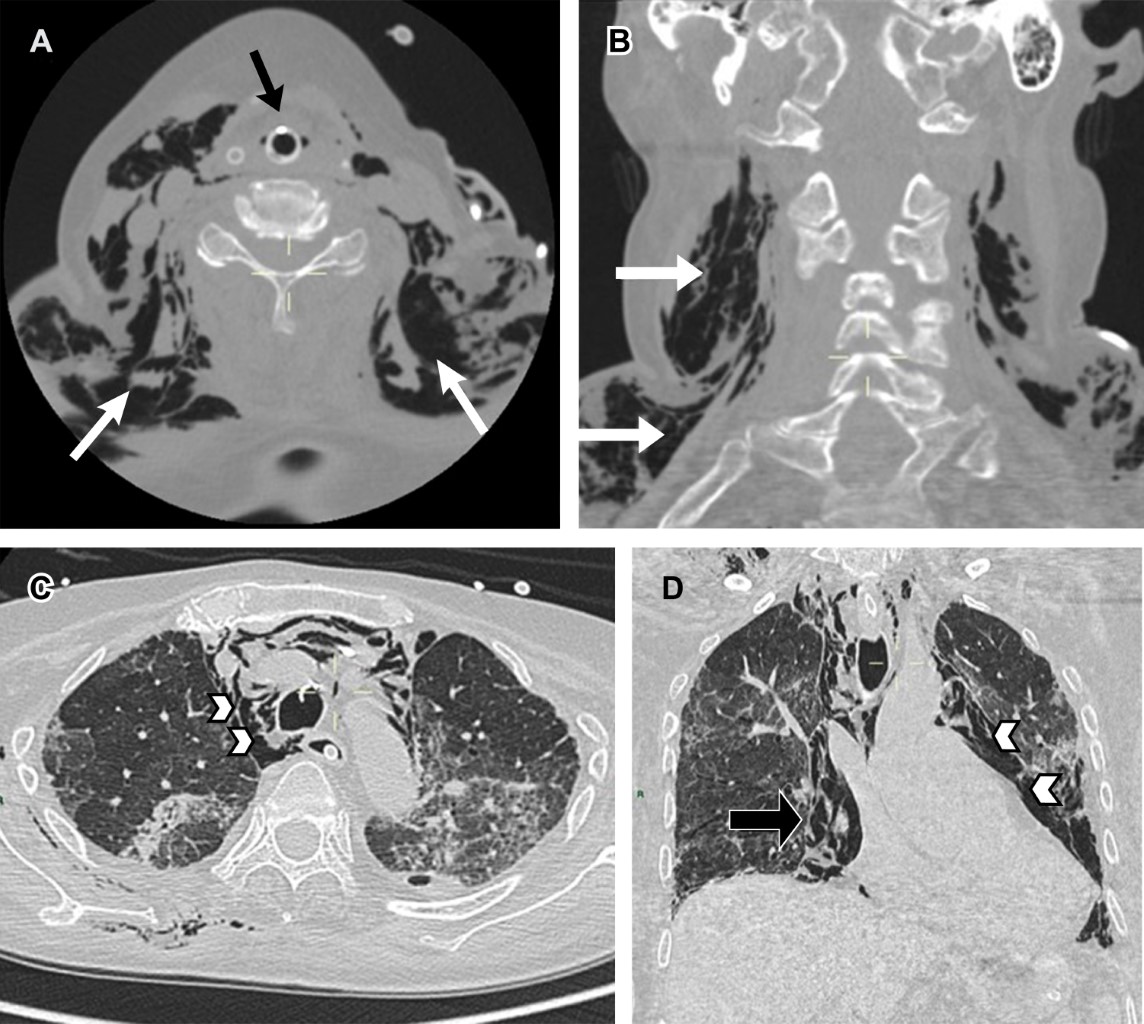

La situación ideal del tubo endotraqueal está dada por la distancia entre el extremo distal y la carina; en la literatura se considera que la posición correcta es de entre 3 y 7 cm superior a ésta, con el cuello en posición neutra, ya que con la extensión o la flexión del mismo es posible modificar la altura de la punta del tubo de hasta 2 cm de diferencia.6-8 También se describe la relación con las cuerdas vocales, considerando una distancia óptima de 3-4 cm inferior a esta estructura para evitar lesión o extubación espontánea.1,3,9 La tomografía y resonancia magnética son las modalidades de imagen ideales para su evaluación.

Cuando no se logra identificar la carina, debemos recordar que normalmente se encuentra entre los cuerpos vertebrales T5 y T7 en 95% de los pacientes.1 Existen otros marcadores anatómicos para determinar si el extremo distal del tubo tiene una posición óptima, y podemos usar de referencia los cuerpos vertebrales T2-T4,6,8 los bordes mediales de las clavículas o la porción caudal del arco aórtico (Figura 1A y B).10

• 1. Intubación selectiva. Si el tubo endotraqueal sobrepasa los marcadores anatómicos antes descritos, existe el riesgo de realizar una intubación bronquial selectiva, generalmente al bronquio principal derecho.3,6 Esto conduce al colapso del pulmón contralateral, e hiperinflación o neumotórax del pulmón ipsilateral (Figura 1C).6

También puede presentarse intubación esofágica, que se sospecha si en la radiografía de tórax se observa el tubo endotraqueal radiopaco lateral a la columna radiolúcida que corresponde al aire de la tráquea, la proyección del tubo por debajo de la carina, o sobredistensión del estómago.3,8 Para confirmar la posición del tubo se utiliza la proyección oblicua posterior derecha, ya que el esófago se encuentra posterior a la tráquea.3

La lesión faríngea se asocia a intentos múltiples de intubación en pacientes con vía aérea difícil, observando la aparición tardía de enfisema subcutáneo o neumotórax.11 Las estructuras que forman la laringe también pueden involucrarse secundario a la presión ejercida del extremo distal del dispositivo durante el paso por las cuerdas vocales, aunque es poco frecuente. Entre estas complicaciones destacan la dislocación del cartílago aritenoideo en sentido posterolateral o anteromedial,11 que se caracteriza en las imágenes y reconstrucciones multiplanares de la tomografía simple por la asimetría en la altura de las cuerdas vocales.12 De forma crónica, esta condición desencadenará disfonía.

En cuanto a la anatomía, destacamos que la pared posterior de la tráquea es membranosa predisponiéndola al trauma, cuando la lesión se asocia al dispositivo endotraqueal el sitio de lesión más común es éste. Los hallazgos radiológicos incluyen neumotórax bilateral, enfisema subcutáneo masivo (si la lesión involucra la hipofaringe el aire se extiende y diseca la región cervical)1 y neumomediastino (Figura 2).8,14,15